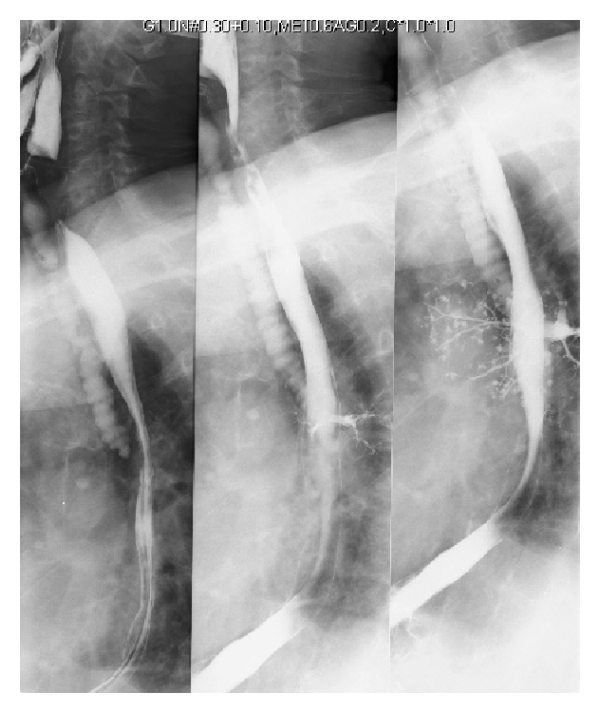

투시경 검사 연하 검사는 연하곤란 또는 운동 장애가 흡인의 원인으로 생각되는 경우에 수행할 수 있다. 음식과 음료를 바륨 조영제와 혼합하여 X-레이를 사용하여 연하를 평가한다. 조영제가 성대 아래로 기관으로 흘러 들어가는 경우 흡인으로 진단할 수 있다.[13]